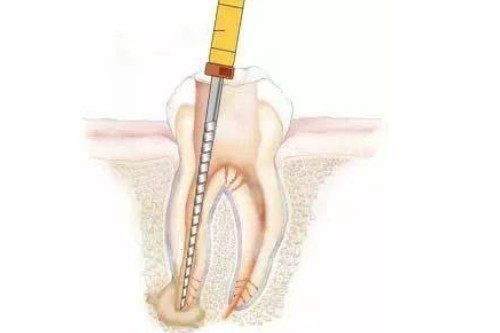

根管治疗

前牙根管治疗:680元起/颗

后牙根管治疗:1500元起/颗

乳牙根管治疗:800元起/颗

显微根管治疗:2000元起/颗

根尖诱导术:500元起/颗